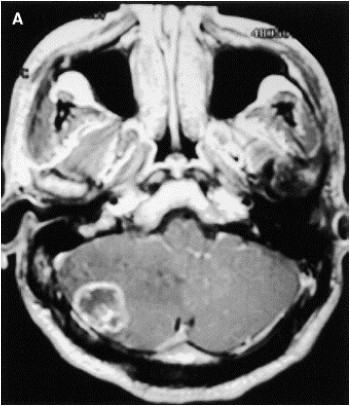

Considere um paciente masculino 55 anos com historia de hemiparesia direita há 2 semanas, sem nenhum fato significante de antecedente.

De acordo com a imagem acima, dentre os diagnósticos abaixo descritos, qual o mais provável?

Considere um paciente masculino 55 anos com historia de hemiparesia direita há 2 semanas, sem nenhum fato significante de antecedente.

De acordo com a imagem acima, dentre os diagnósticos abaixo descritos, qual o mais provável?